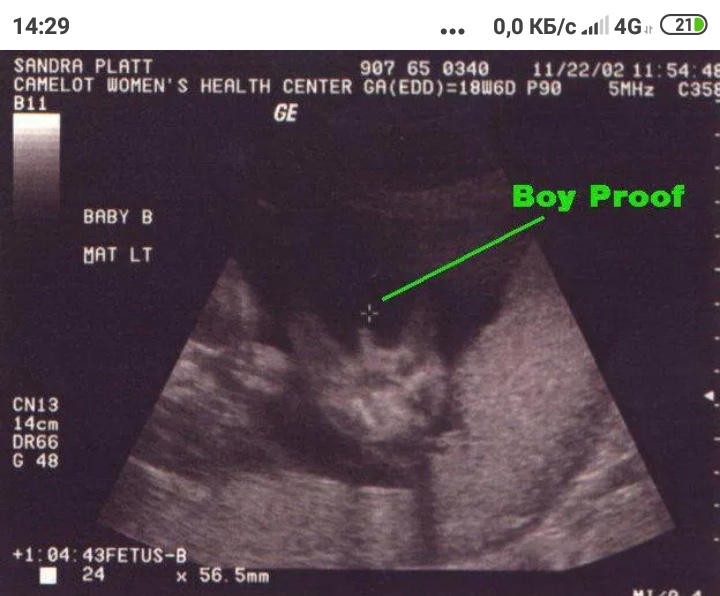

Пол на 14 неделе беременности по узи

Пол на 14 неделе беременности по узи 88 фото